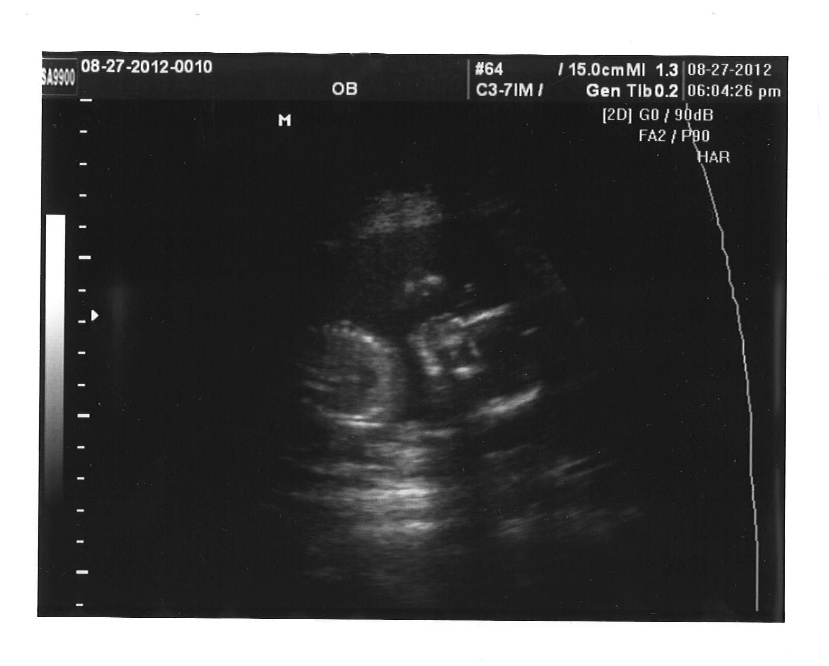

Attachment 4274

I just could not wait... so I called up the U/S place and got in tonight!!!!

But it's confirmed ladies, IT'S A GIRL!!!!!!! :running:

There were three lines the whole time... nothing between her little legs!

Bare with me while I figure out how to get the pics up

I am just in shock and OVER THE MOON! The tech was an OB from Europe and he has been doing this for years and he was working at that place a few years ago because we saw him there.

He told us that he is the owner! So that made me Very happy! DH Is VERY Happy Too!